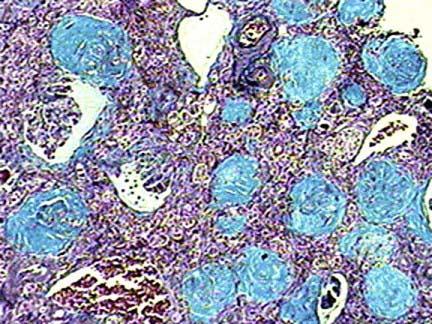

问题 患者女性,69岁,肾功能不全进行性发展5年,肾脏严重萎缩,手术切除见双肾对称性缩小,表面颗粒状,切面皮质变薄;镜检如图所示,如图分别为HE染色和Masson染色,正确的诊断是 ( )

选项 A.慢性肾盂肾炎 B.慢性肾小球肾炎 C.弥漫性肾皮质坏死 D.急性肾小球肾炎 E.急性肾盂肾炎

答案 B